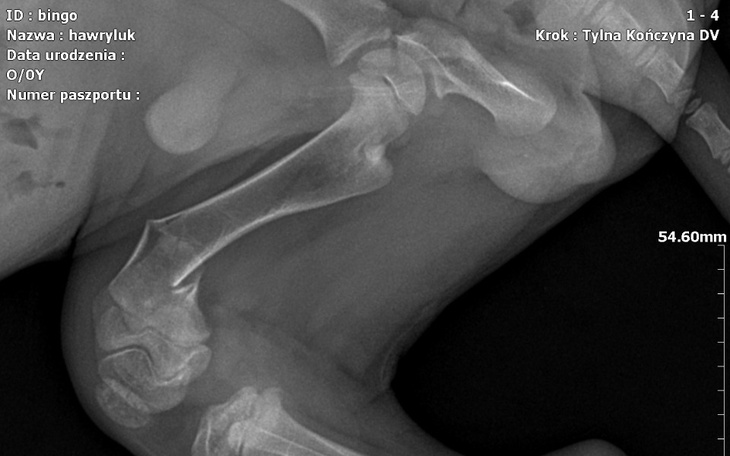

Bingo zabrany ze schroniska w Chełmie 22.11.2023r dnia 26.11.2023 Bingo został przebadany przez dwóch weterynarzy na Browarnej i w Animed gdyż wymiotował krwią i robił kupy z krwią okazało się że postępującą ma parwowirozę nie jadł nie pił był odwodniony wtedy zaczęła się nasza walka o naszego przyjaciela miał podawana surowicę przeszczep kału i założona była sonda Bingus dzielnie walczył do dnia dzisiejszego.Dnia 30.12.2023 dziecko wyszło na spacer z naszym Bingiem obok bloku nikt nie spodziewał się że stanie się krzywda gdyż do dziecka biegł duży pies córka ze strachu wzięła Binga na ręce i nie fortunnie upuściła Binga i dostał złamania kości prawej tylniej niestety RTG potwierdziło złamanie i trzeba przeprowadzić operację to są kolejne koszty leczenia Binga dzięki pomocy ludziom o dobrym sercu i walka i wiara w Binga wygrał z parwowiroza teraz też będziemy walczyć do końca o Bingusia by nie był kaleką wszystkie faktury będą dołączane prosimy o każdy grosz